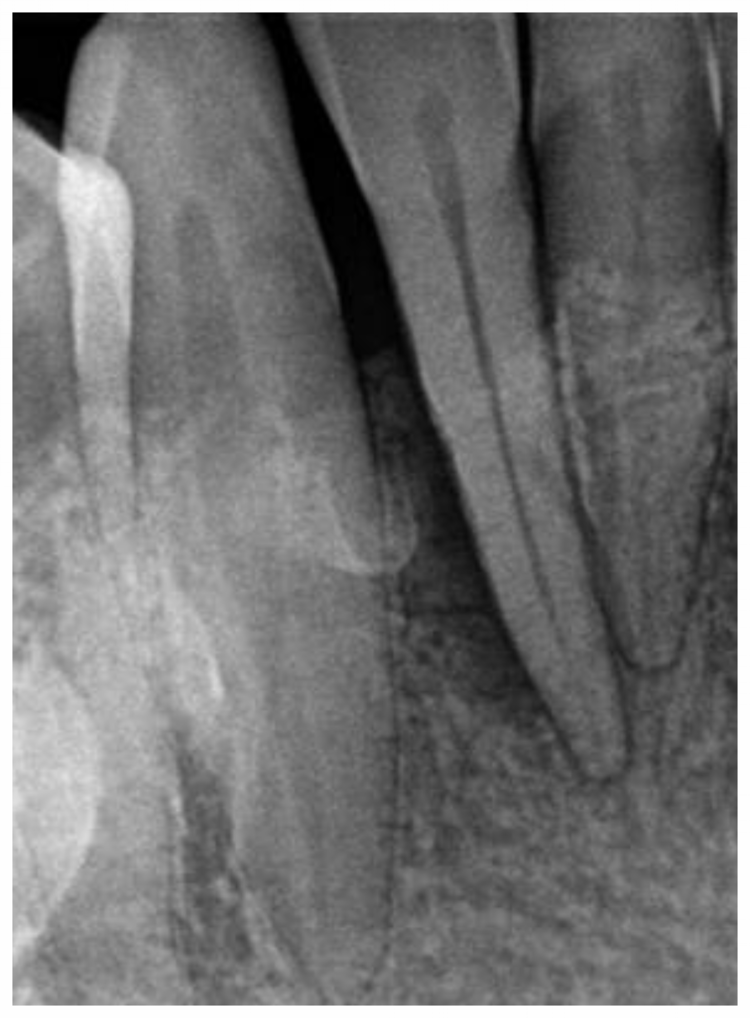

Before After

The before and after x-rays of the front tooth demonstrating a healthy bone refill. This is an exceptional result using non-surgical treatment. Perioscopy allowed us to both save this tooth from extraction and the smile of the patient.